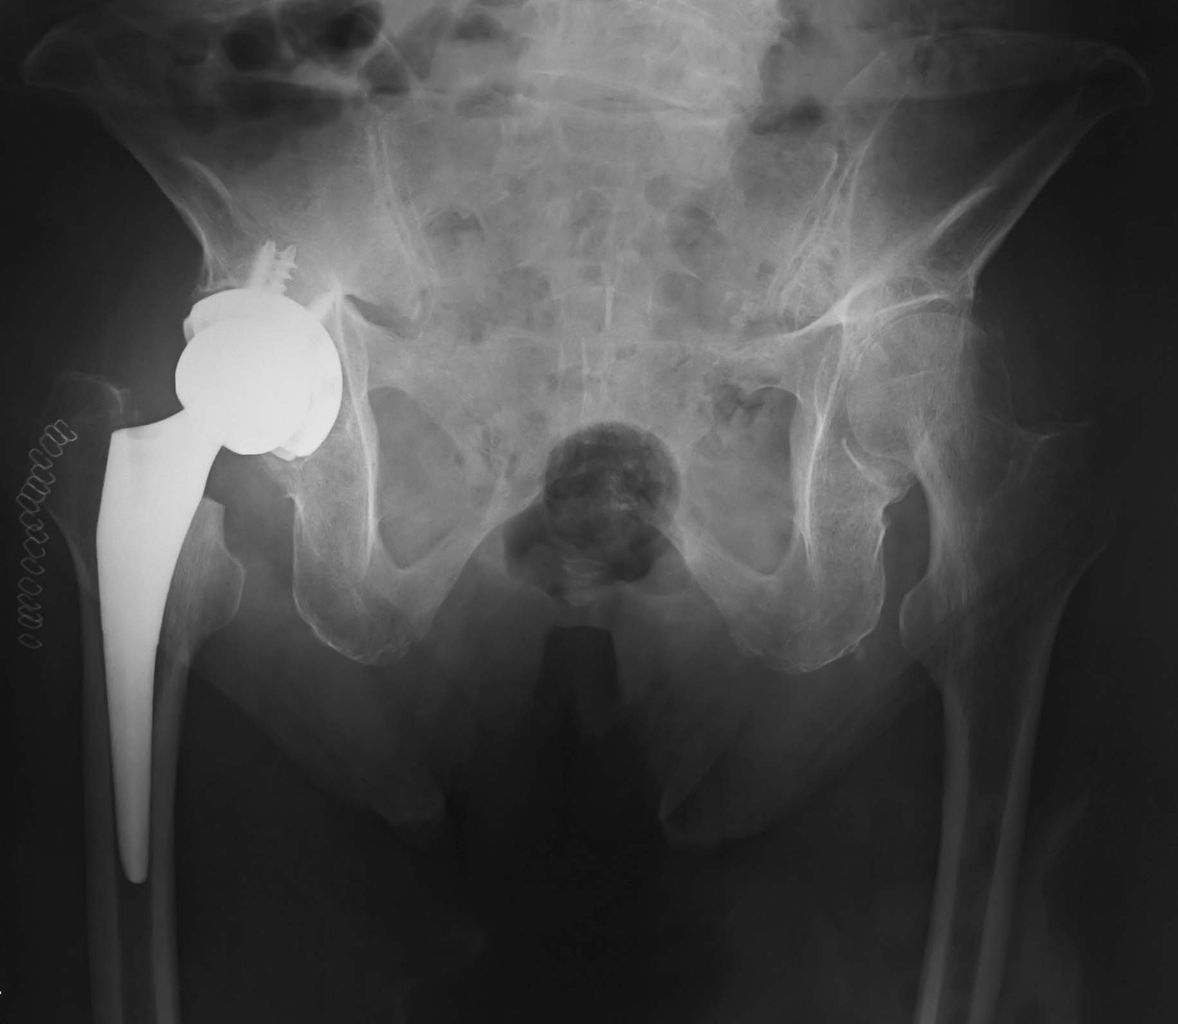

先日、急速破壊型股関節症(RDC)に対して人工股関節全置換術を施行しました。今回の患者さんは80歳を超える高齢者で、著明な腰椎後弯と骨盤後傾を認めました。

このため、術中のカップ設置の際には少し勇気が要りますが、できるだけ前方開角を減じてインパクションするようにしています。骨盤後傾症例は難しいですね。